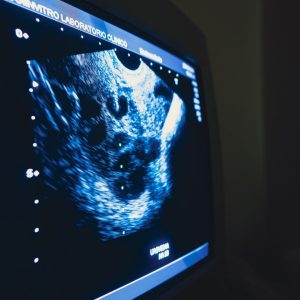

• Consultas e Controles de ultrassonografias;